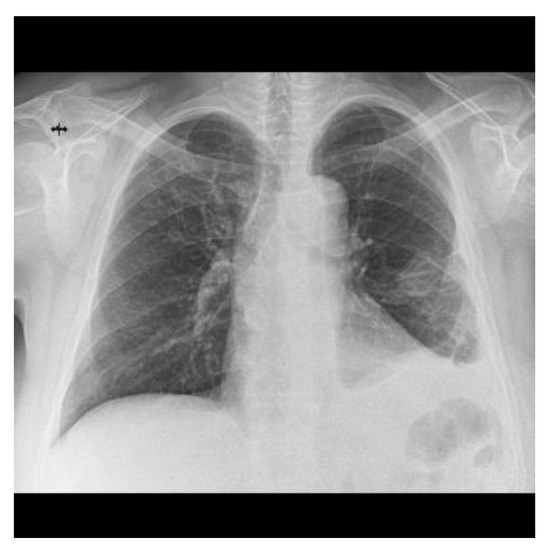

2.2. Blood Workup, Functional Tests, Bronchoscopy, and Radiological Findings